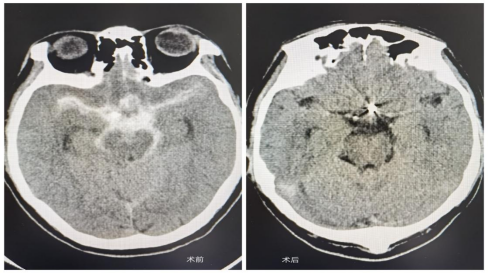

2025年3月我市赵先生突发剧烈头痛就诊我院,首诊医师神经外科主治医师荆泽林急查头部CT提示蛛网膜下腔出血,Hunt-Hess 2级。科室集体讨论考虑颅内动脉瘤破裂致蛛网膜下腔出血,荆泽林医生安排患者急诊行脑血管造影术。术中证实术前判断,科主任王伟志、主任医师云亚滨考虑患者前交通动脉瘤破裂致蛛网膜下腔出血,征得家属同意,进一步行经导管颅内动脉瘤栓塞术(微创手术)。

术中采取双微导管技术对动脉瘤进行填塞。双微导管技术巧妙地将两根微导管导入动脉瘤腔内,在同一动脉瘤内形成两个不同的操作通道。这一设计,极大地提高了栓塞治疗的灵活性和精确性,让治疗过程更可控。在传统动脉瘤栓塞治疗中,因动脉瘤形态不规则,弹簧圈难以稳定放置,极易出现移位、栓塞不全的问题,导致治疗效果欠佳,复发风险居高不下,双微导管技术彻底改变了这一局面。

手术顺利,术后患者神清、语利,四肢活动良好,无任何后遗症,恢复如初。